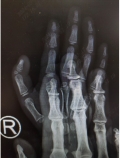

他们选择了betway在线登陆小儿骨科,这里有经验丰富的医疗团队和先进的医疗设备。滕道练副主任医师接待了乐乐一家,他仔细查看了患者的手指情况,并拍摄了X线片进行进一步的诊断。经过专业的检查,滕医生确定乐乐的情况为先天性三节拇指,这是一种常染色体显性遗传疾病,有44%的患者有明显的家族史。

乐乐的拇指偏斜程度虽然不是很严重,但这并没有引起家人的重视。他们尝试了保守治疗,但效果并不理想。面对这种情况,唯一能够解决问题的方法就是手术。滕医生根据乐乐的具体情况,设计了一套手术方案。手术中,医生将拇指中节的“Delta”骨去除,进行了韧带紧缩修复,并使用克氏针固定,以改善拇指的外形。